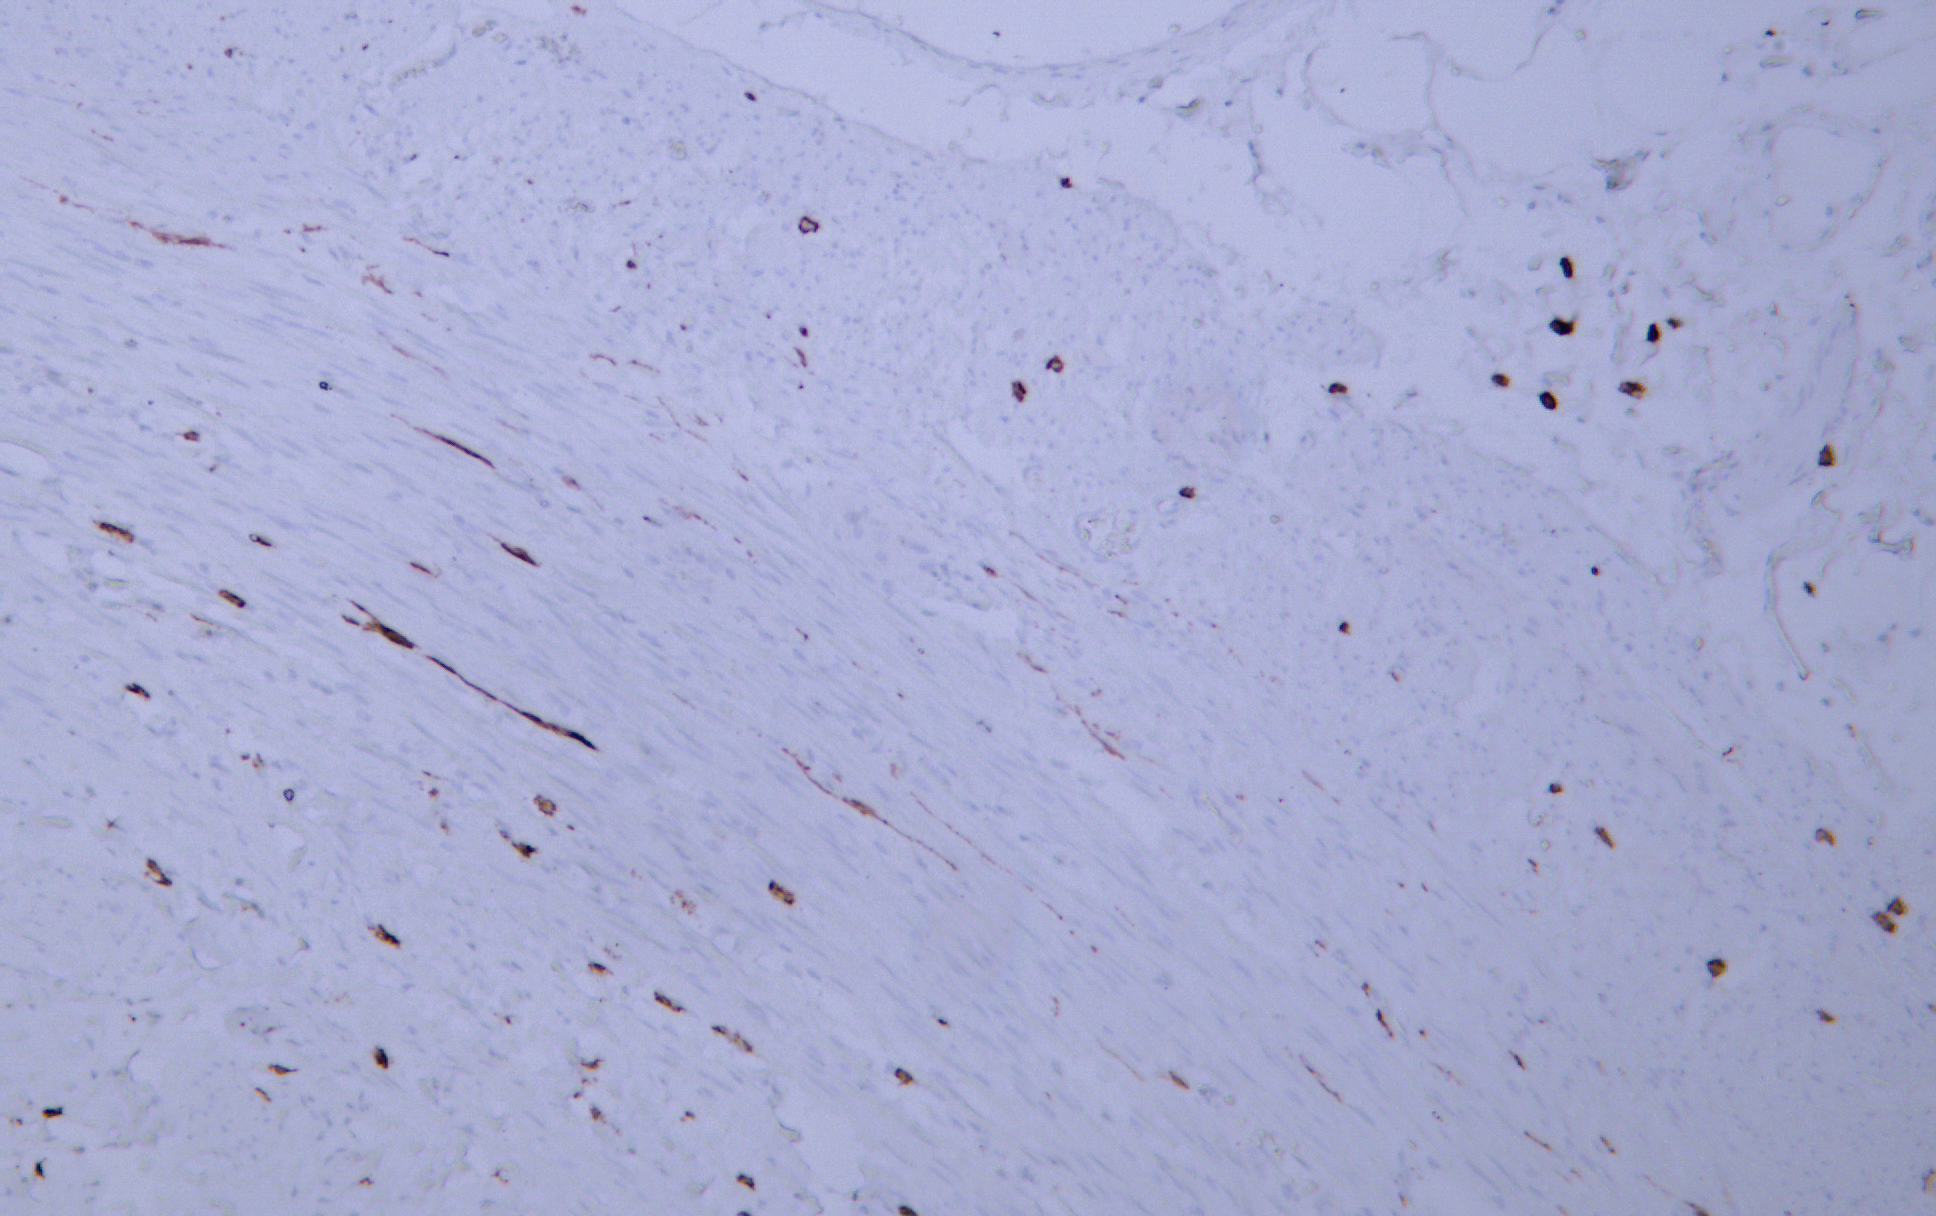

CD117 is a cell membrane protein encoded by the c-kit proto-oncogene and is a type III transmembrane protein tyrosine kinase growth factor receptor. CD117 is expressed in mast cells, melanocytes and interstitial cells of Cajal. CD117 is positive in 80-100% of gastric stromal sarcoma (GIST) . CD117, as a specific marker for immunohistochemical examination of gastric stromal sarcoma (GIST) , can be used to clinically guide the personalized target drug (Gleevec) treatment of GIST patients. CD117 can also be used to identify mast cell tumors in lymphoma and as a marker for some testicular germ cell tumors.

IHC; WB; IF; ELISA

IHC, 1:200-1:1000 | WB, 1:500-1:2000 | IF, 1:100-1:500 | ELISA, Recommended starting concentration is 1 µg/mL. Please optimize the concentration based on your specific assay requirements.